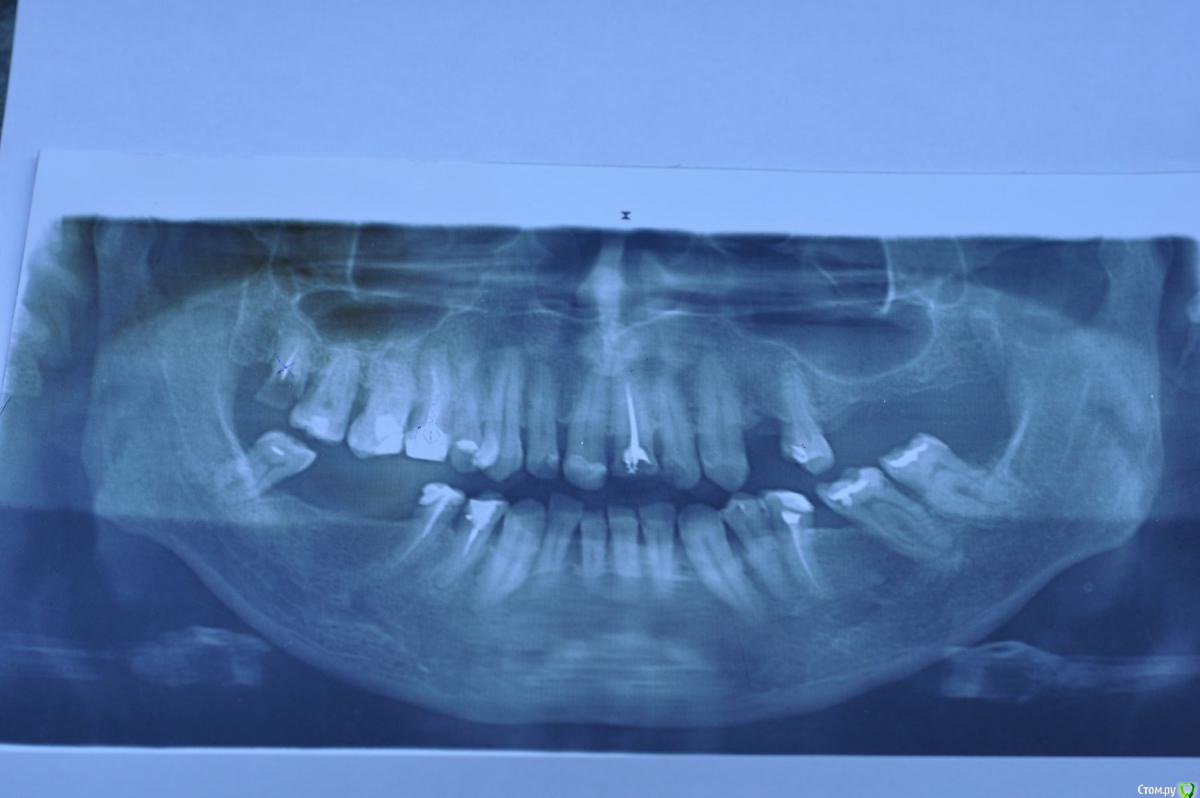

Родион Р. Опубликовано 14 июня, 2015 Поделиться Опубликовано 14 июня, 2015 Обращаюсь к профессионалам за помощью и советом. Был в 6-ти клиниках по поводу протезирования. В итоге растерялся среди многообразия вариантов плана лечения ( разброс цен от 35 до 200 т.р.). Нет ясности что делать с 1) 11 и 21 , 2) 16 и 15, 3) 23 и 25, 3) 48 и 45. Основной критерии а) необходимо и достаточно, б) надежность и функциональность, на последнем - красота. Убедительно прошу помощи по составлению профессионального плана. Заранее благодарю. Ссылка на комментарий

M@estro Опубликовано 14 июня, 2015 Поделиться Опубликовано 14 июня, 2015 1) перелечивание 16,1.5,2.1, 35,4.4,4.5.2) санация, удаление 1.83) установка имплантатов в области 2.4,2.6,2.7,4.6,4.7.+ синус-лифтинг4) покрытие депульпированных зубов одиночными коронками, изготолвеие коронок на имплантаты. 5) для эстетики - замена пломб во фронтальном отделе на непрямые реставрации. 2 Ссылка на комментарий

Vladimirov Опубликовано 14 июня, 2015 Поделиться Опубликовано 14 июня, 2015 1) перелечивание 16,1.5,2.1, 35,4.4,4.5. 2) санация, удаление 1.8 3) установка имплантатов в области 2.4,2.6,2.7,4.6,4.7.+ синус-лифтинг 4) покрытие депульпированных зубов одиночными коронками, изготолвеие коронок на имплантаты. 5) для эстетики - замена пломб во фронтальном отделе на непрямые реставрации. это уже от 200тр Ссылка на комментарий

Mailze Опубликовано 16 июня, 2015 Поделиться Опубликовано 16 июня, 2015 Спасибо за ответ! Вы правы, имея опыт с эндопротезированием сустава и не имея возможности приехать на лечение к Вам, я прошу Вас как профессионала альтернативный план лечения ( без имплантации). Чтобы взяв план за основу, как фундамент произвести лечение учитывая ньюансы которые можно определить только на очном приеме.( Вы даже не представляете себе, что в провинции нет узких специалистов, я не имею в виду стоматологию.) Заранее благодарю. Адаптировал план лечения профессионала M@estro под Ваши требования, только учтите, что этот план лечения не оптимальный, а компромиссный.1) удаление 1.82) перепломбировать корневые каналы 16, 1.5, 2.1, 3.5, 4.4, 4.5., санация,3) покрытие депульпированных зубов одиночными коронками,4) бюгельный протез с кламмерной фиксацией на верхнюю и нижнюю челюсть5) для эстетики - замена пломб во фронтальном отделе на непрямые реставрации. Ссылка на комментарий